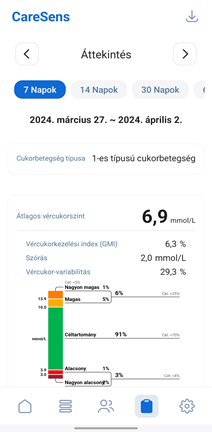

Sens365 alkalmazás

Megoszthatók a diabétesz kezeléséhez szükséges különböző terápiás adatok, cukorértékek és trendek.

* Az alkalmazás képernyője a szoftver verziójától függően eltérhet.